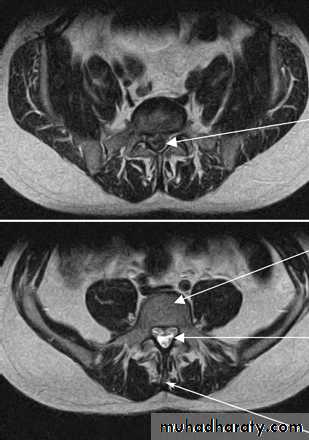

• Incomplete• Cauda Equina syndrome:

• # Saddle anesthesia, urinary retention and stool incontinence.

• # Usually due to large central disc herniation rather than fracture.

• Nerve root deficit: LMN

Cauda Equina Syndrome

A surgical emergency.Requires full neurologic examination including rectal examination for anal tone.

Investigations: X-rays initially, but MRI is mandatory as X-rays are usually unremarkable.

Treatment: Emergency decompression-usually discectomy and wide laminectomy within 24 hours.